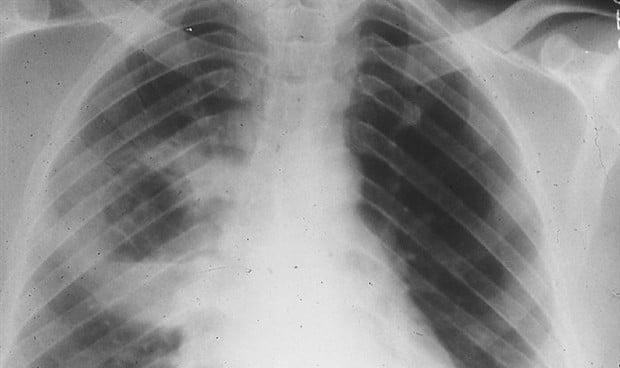

Algunos de los pacientes contagiados por el Covid-19 desarrollan una lesión pulmonar irreversible. Para estos casos que no pueden ser retirados de la ventilación mecánica, el trasplante de pulmón surge como única opción para salvarle la vida. Un estudio revela que tras el trasplante que se hizo a tres pacientes que tenían insuficiencia respiratoria asociada al coronavirus el ARN del SARS-CoV-2 no pudo detectarse en los pulmones explantados, pero se observaron patología fibrótica y cambios transcripcionales que se asemejan a los de los pulmones de pacientes con fibrosis pulmonar.

Tras los primeros exámenes, los científicos detectaron que los pulmones de estos cinco pacientes contagiados por el virus estaban libres de SARS-CoV-2 según lo detectado por smFISH, pero la patología "mostró evidencia extensa de lesión y fibrosis que se asemejaba a la fibrosis pulmonar en etapa terminal”, explican los investigadores. En esta línea, los autores del estudio explican que algunos pacientes con Covid-19 grave desarrollan enfermedad pulmonar fibrótica para la cual el trasplante de pulmón es su única opción de supervivencia.